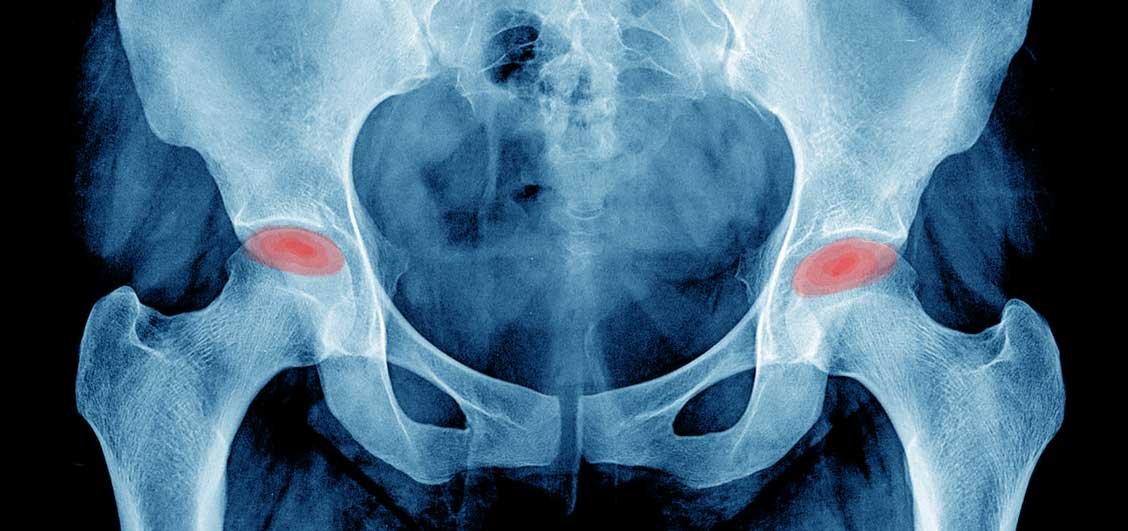

نكروز رأس عظمة الفخذ هو تَمَوت (نكروز او تنخر) رأس عظمة الفخذ (ويعرف أيضاً بالنخر اللاوعائي أو موت أو نقص التروية الدموية لعظمة رأس الفخذ Avascular necrosis of the femoral head ) هى حالة تؤدي إلى ضمور أو موت رأس عظمة الفخذ نتيجة عدم وصول الدم إليها وبالتالي تموت رأس العظمة وتتسطح بحيث تفقد إستدارتها.

و مع إستمرار الإحتكاك مع المشي والحركة يحدث تآكل في غضاريف المفصل مما يؤدي الى حدوث خشونة،وذلك في حالة عدم علاج نخر عظم الورك، وبالتالي الشعور بآلام حادة عند تحريك مفصل الفخذ. وقد يظهر هذا المرض بعد فترة في مفصل الفخذ الآخر.

يمر المرض بأربعة مراحل كما فى الشكل التالي:

- المرحلة الأولى: في هذه المرحلة لا يشكي المريض ألمًا في الأغلب أو ربما يشكو ألمًا بسيطًا، ولكن مع تقدم المرض يبدأ الألم فى الزيادة خصوصًا مع الوقوف والمشي. وتبدو الأشعات السينية طبيعية فى هذه المرحلة. و يتم اللجوء لأشعة الرنين المغناطيسي لبيان موضع وحجم الجزء الذي لا يصلة الدم. كما قد يحتاج المريض لعمل مسح ذري للتأكد من التشخيص.

- المرحلة الثانية: يظهر في الاشعة العادية تغيرات فى نسيج عظام رأس عظمة الفخذ ولكن رأس العظمة تظهر كاملة الإستدارة.

- المرحلة الثالثة: يظهر تسطح لرأس عظمة الفخذ فى الاشعة السينية ولكن دون حدوث خشونة (تآكل للغضاريف) بمفصل الفخذ.

- المرحلة الرابعة: توجد خشونة ظاهرة بمفصل الفخذ. نتيجة تآكل الغضاريف المبطنة للمفصل.